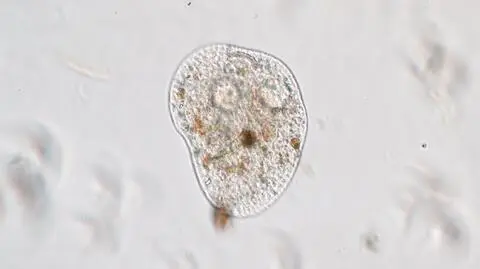

Pierwotniak Naegleria fowleri, bo o nim mowa, jest jednokomórkowym organizmem żyjącym w wodach słodkich, ale można znaleźć go też w basenach. Do zakażenia dochodzi, kiedy dostaje się on do organizmu człowieka przez nos. Doprowadza do infekcji nazywanej ostrym pierwotnym amebowym zapaleniem mózgu i opon mózgowo-rdzeniowych. Zakażenie jest rzadkie, ale na tyle groźne, że w większości przypadków kończy się śmiercią. Pierwsze objawy pojawiają się od jednego do siedmiu dni po zakażeniu. Chorzy skarżą się na bóle głowy, gorączkę, wymioty i sztywność karku. Później dochodzą problemy z koncentracją, utratą równowagi, pojawiają się także drgawki i halucynacje. Po tych symptomach postęp choroby jest bardzo szybki i gwałtowny.